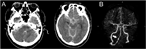

Overlapping stent-assisted coil embolization for a ruptured intracranial vertebral artery dissection

Katsunori Asai and others

Journal of Surgical Case Reports, Volume 2017, Issue 6, June 2017, rjx105, https://doi.org/10.1093/jscr/rjx105